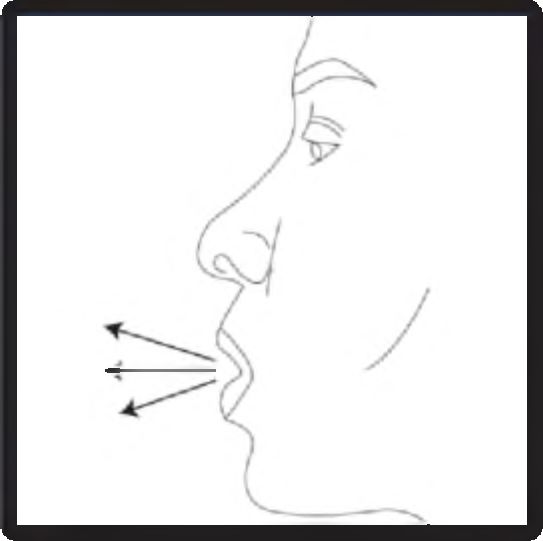

6. Nefesinizi kuvvetlice dışarı verin.

7. Ağız parçasını ağzınıza yerleştirin ve başınızı hafifçe geriye eğin. Ağız parçası etrafında dudaklarınızı sıkıca kapatın ve olabildiğince hızlı ve derin bir nefes alın. Toz dağılırken kapsülün bölmesinde dönmesinden kaynaklanan bir “vızıltı” sesi duyacaksınız. Bu sesi duymadıysanız kapsül bölmesinde sıkışmış olabilir. Bu durumda cihazı açınız ve kapsülü bölmesinde oynatarak gevşetiniz. Kapsülü gevşetmek için düğmelere birden fazla BASMAYINIZ.

8. Vızıltı sesini duyduktan sonra cihazı ağzınızdan çıkarırken nefesinizi rahatsız olmadan olabildiğince uzun süre içinizde tutun. Daha sonra normal şekilde nefes almaya devam edin. Cihazı açarak kapsülün içinde toz kalıp kalmadığını kontrol edin. Kapsülün içinde toz kalmışsa, 6, 7 ve 8. basamakları tekrarlayın.